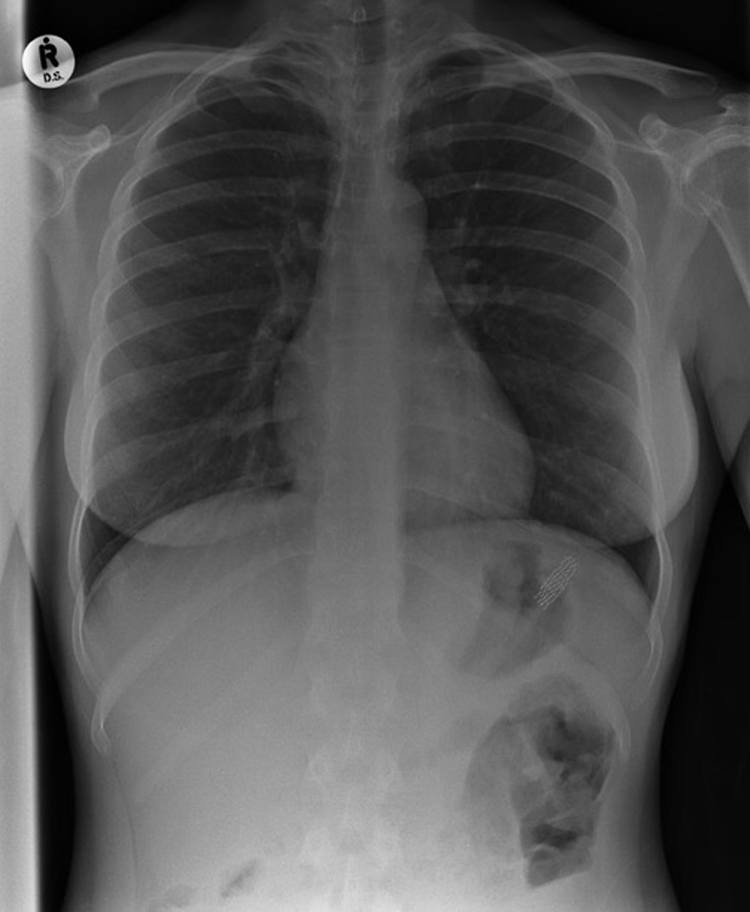

18. A Seven Inch Kidney Stone

This kidney stone seems so huge that it could not possibly be real. But it is. This kidney stone was found inside a patient in Hungary and it was a massive 7-inches long and wide. Thankfully, it was successfully removed which was a huge relief to the patient.Advertisement